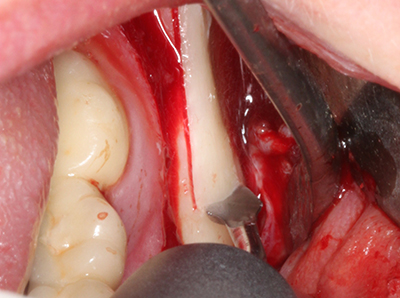

El tejido óseo no solo tiene un contenido puramente mineral, sino que también presenta una importante proporción de fibras de colágeno. Esto no solo garantiza una buena resistencia a la presión, sino también una cierta flexibilidad, que puede aprovecharse para la realización de aumentos. En la plastia de expansión clásica a efectos de una partición ósea, la cresta maxilar atrofiada se divide en su eje longitudinal y, tras alcanzar una profundidad de osteotomía suficiente, se extiende con cuidado (fig. 13-16), en un caso ideal sin desperiostizar de forma visible el maxilar (Brugnami, Caiazzo et al. 2014, Stricker, Fleiner et al. 2014). Los sistemas de tornillos y placas con distancia de expansión creciente han demostrado su eficacia para distanciar entre sí las dos tablas óseas por debajo del umbral de rotura. Por regla general, se requieren anchuras de hueso residual de al menos 3 a 4 mm (Chiapasco, Zaniboni et al. 2006) para garantizar una flexibilidad y una cobertura ósea suficientes de los implantes que van a incorporarse. En caso necesario, una osteotomía de descarga vertical unilateral o bilateral puede mejorar la flexibilidad. Como alternativa a la técnica clásica se ha descrito una combinación con otras técnicas de aumento, sobre todo en la parte bucal.

Con el uso de sierras piezoeléctricas la división se efectúa de forma especialmente cuidadosa y sin pérdidas importantes de las dimensiones, por lo que no se han encontrado diferencias significativas entre los implantes realizados en el maxilar dividido y en la cresta alveolar no deficitaria (Chiapasco, Zaniboni et al. 2006, Danza, Guidi et al. 2009). No obstante, precisamente en la partición profunda y limitada de forma local, es preciso asegurarse de que exista una adecuada irrigación por agua para evitar que se produzcan sobrecargas térmicas en las áreas de osteotomía apical.